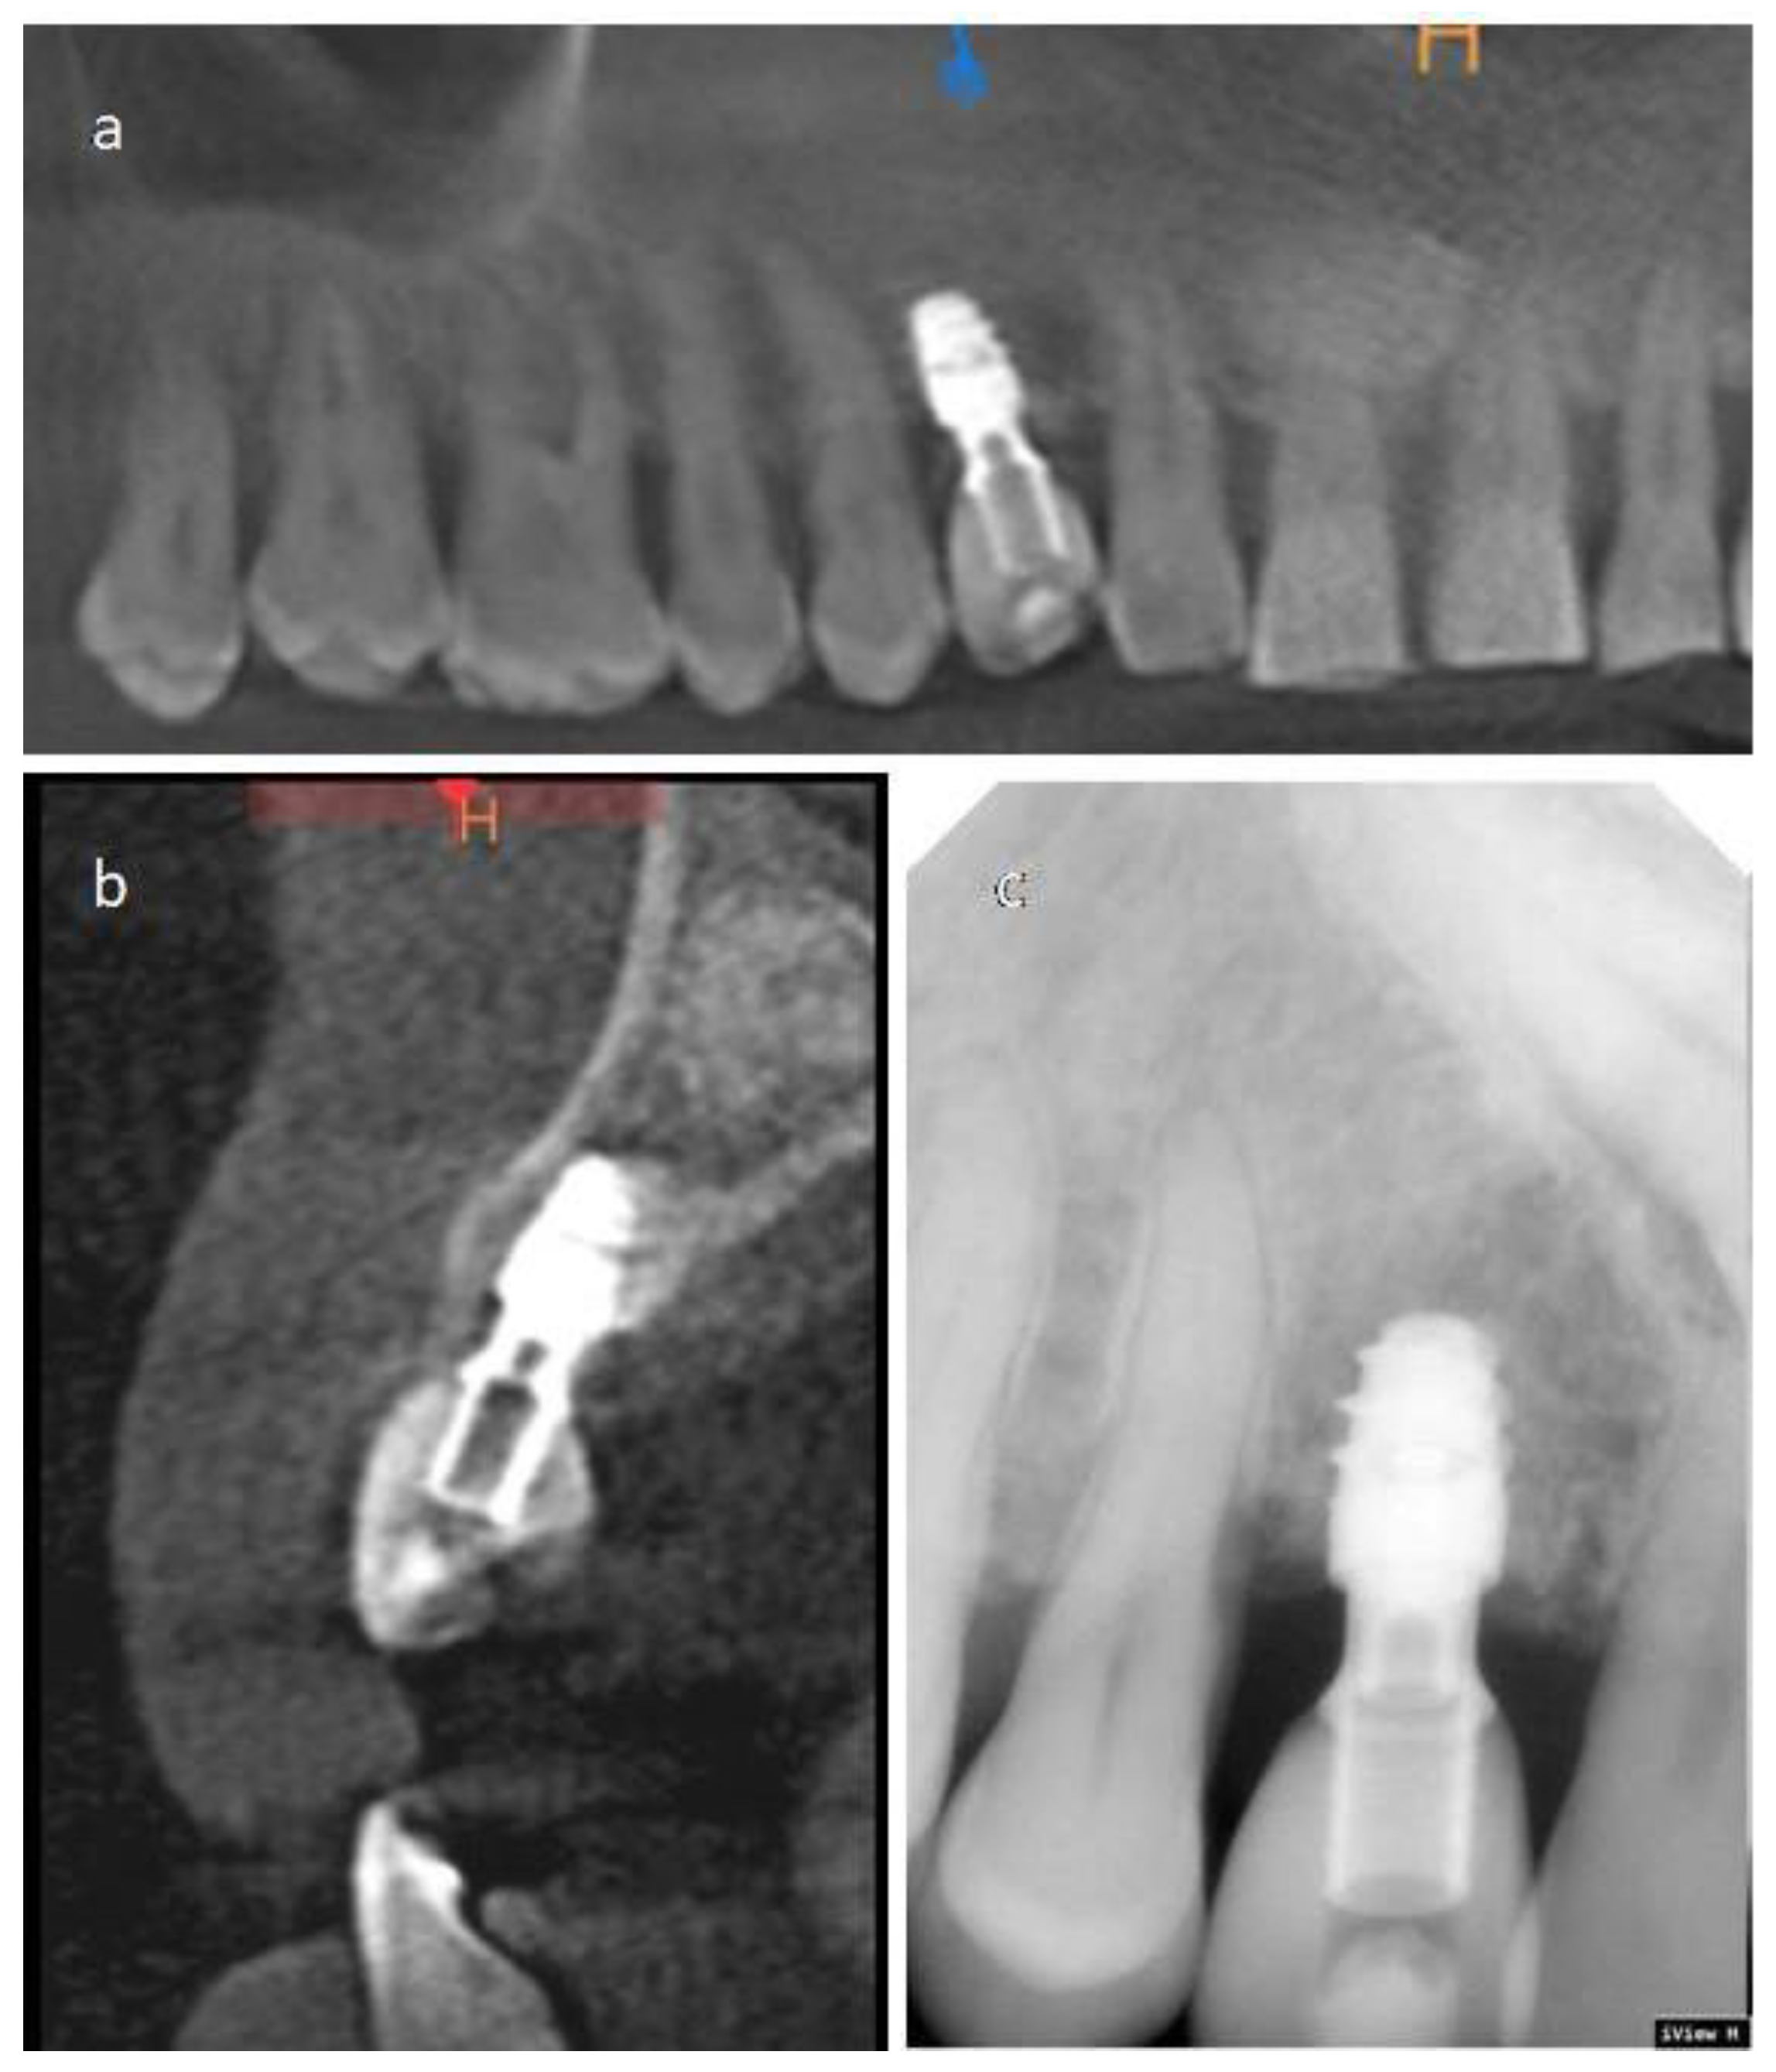

2.2.1. Case 1

2.2.2. Case 2